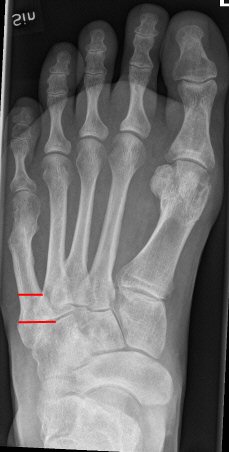

Mellan de röda strecken: ungefärligt läge för Jones-fraktur. Längre proximalt: avulsionsfraktur.

Exempel på Jones-frakturer, första bilden färsk, andra bilden ej läkt, tredje bilden efter operation.